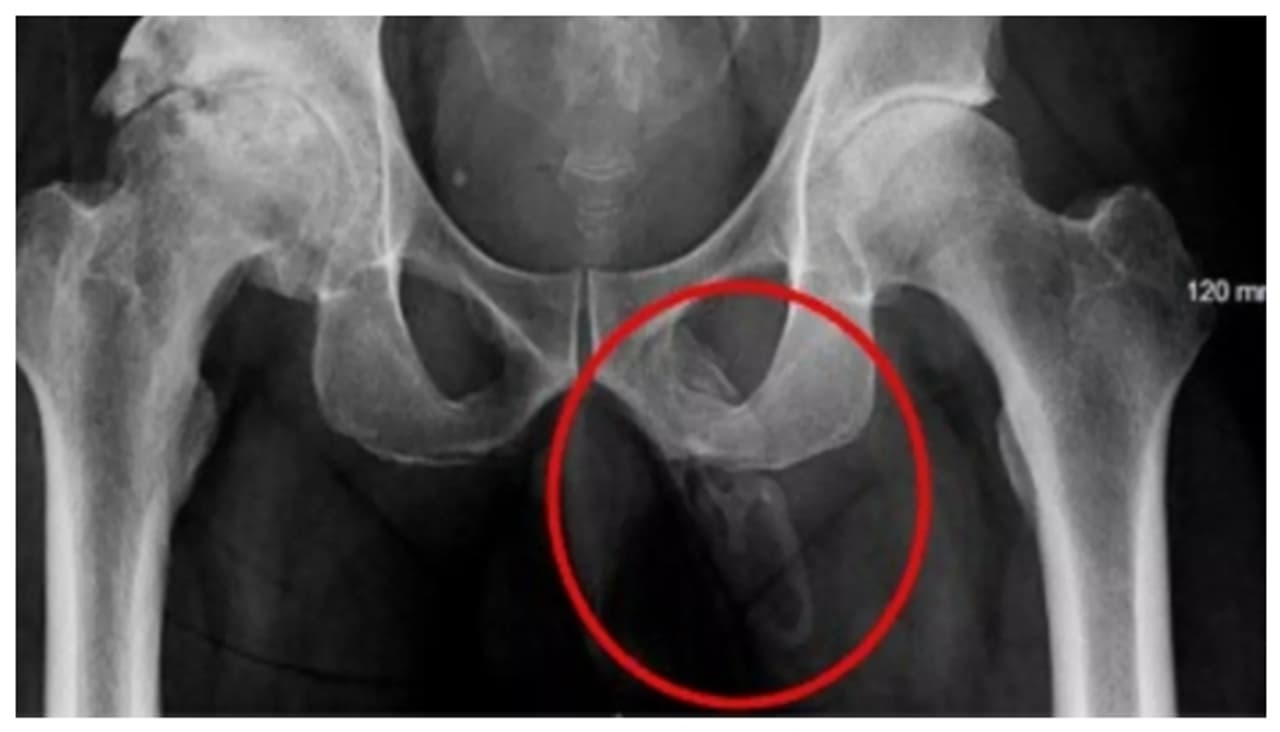

(എക്സ്റേയില് ലഭിച്ച പെനൈൽ ഓസിഫിക്കേഷൻ റിസൾട്ട്)

എക്സ്-റേ സ്കാനിൽ ജനനേന്ദ്രിയം മൃദുവായ ടിഷ്യൂകളിൽ ഗുരുതരമായ കാൽസിഫിക്കേഷൻ സംഭവിച്ചതായി ഡോക്ടര്മാര് കണ്ടെത്തി. "എക്സ്ട്രാസ്കെലെറ്റൽ ബോൺ" (Extraskeletal Bone) എന്നാണ് ഈ പ്രതിഭാസം വൈദ്യശാസ്ത്ര മേഖലയില് അറിയപ്പെടുന്നത്. കാൽസ്യം ലവണങ്ങൾ ജനനേന്ദ്രിയത്തിൽ ഒരു ഫലകത്തോട് സാമ്യമുള്ള രീതിയിൽ നിക്ഷേപിക്കപ്പെടുന്ന അസ്ഥയാണിത്. അത്തരം സന്ദർഭങ്ങൾ അത്യപൂര്വ്വമാണ്. യൂറോളജി കേസ് റിപ്പോർട്ട് പ്രകാരം ഇത്തരത്തിലുള്ള വെറും 40 ൽ താഴെ കേസുകൾ മാത്രമാണ് ഇതുവരെ ലോകത്ത് റിപ്പോര്ട്ട് ചെയ്യപ്പെട്ടിട്ടുള്ളത്.

കാൽമുട്ട് ചികിത്സയ്ക്കെത്തിയ 63 -കാരന്റെ ഇടുപ്പിന്റെ എക്സ്-റേ പരിശോധിച്ച ഡോക്ടര്മാര് അക്ഷരാര്ത്ഥത്തില് ഞെട്ടി. അദ്ദേഹത്തിന് അപൂര്വ്വങ്ങളില് അപൂര്വ്വമായ ജനനേന്ദ്രിയ അസ്ഥിയായി രൂപം മാറുന്ന അസാധാരണമായ രോഗമായ 'പെനൈൽ ഓസിഫിക്കേഷൻ' (Penile Ossification) ആയിരുന്നു ഡോക്ടര്മാര് സ്ഥിരീകരിച്ചത്. 2019-ൽ നടപ്പാതയിൽ വീണ് കാൽമുട്ടിന് അസ്വസ്ഥത അനുഭവപ്പെട്ടതിനെ തുടർന്നാണ് പേര് വെളിപ്പെടുത്താത്ത 63 -കാരനായ രോഗി ന്യൂയോർക്ക് സിറ്റി ഹോസ്പിറ്റലിലെത്തിയത്. വീഴ്ചയില് ബോധക്ഷയമോ തലയ്ക്ക് പരിക്കുകളോ ഒന്നും സംഭവിച്ചിരുന്നില്ല. എങ്കിലും ഭാവിയില് കാല് മുട്ടുവേദനയ്ക്ക് കാരണമായേക്കാവുന്ന ഒടിവോ മറ്റ് പ്രശ്നങ്ങളോ ഒഴിവാക്കാനായി ഡോക്ടർമാർ ഇടുപ്പിന്റെ എക്സ് റേ എടുക്കാന് പറഞ്ഞപ്പോഴാണ് ഈ അസാധരണ രോഗം സ്ഥിരീകരിച്ചതെന്ന് ലാഡ്ബൈബിളില് റിപ്പോര്ട്ട് ചെയ്യുന്നു.